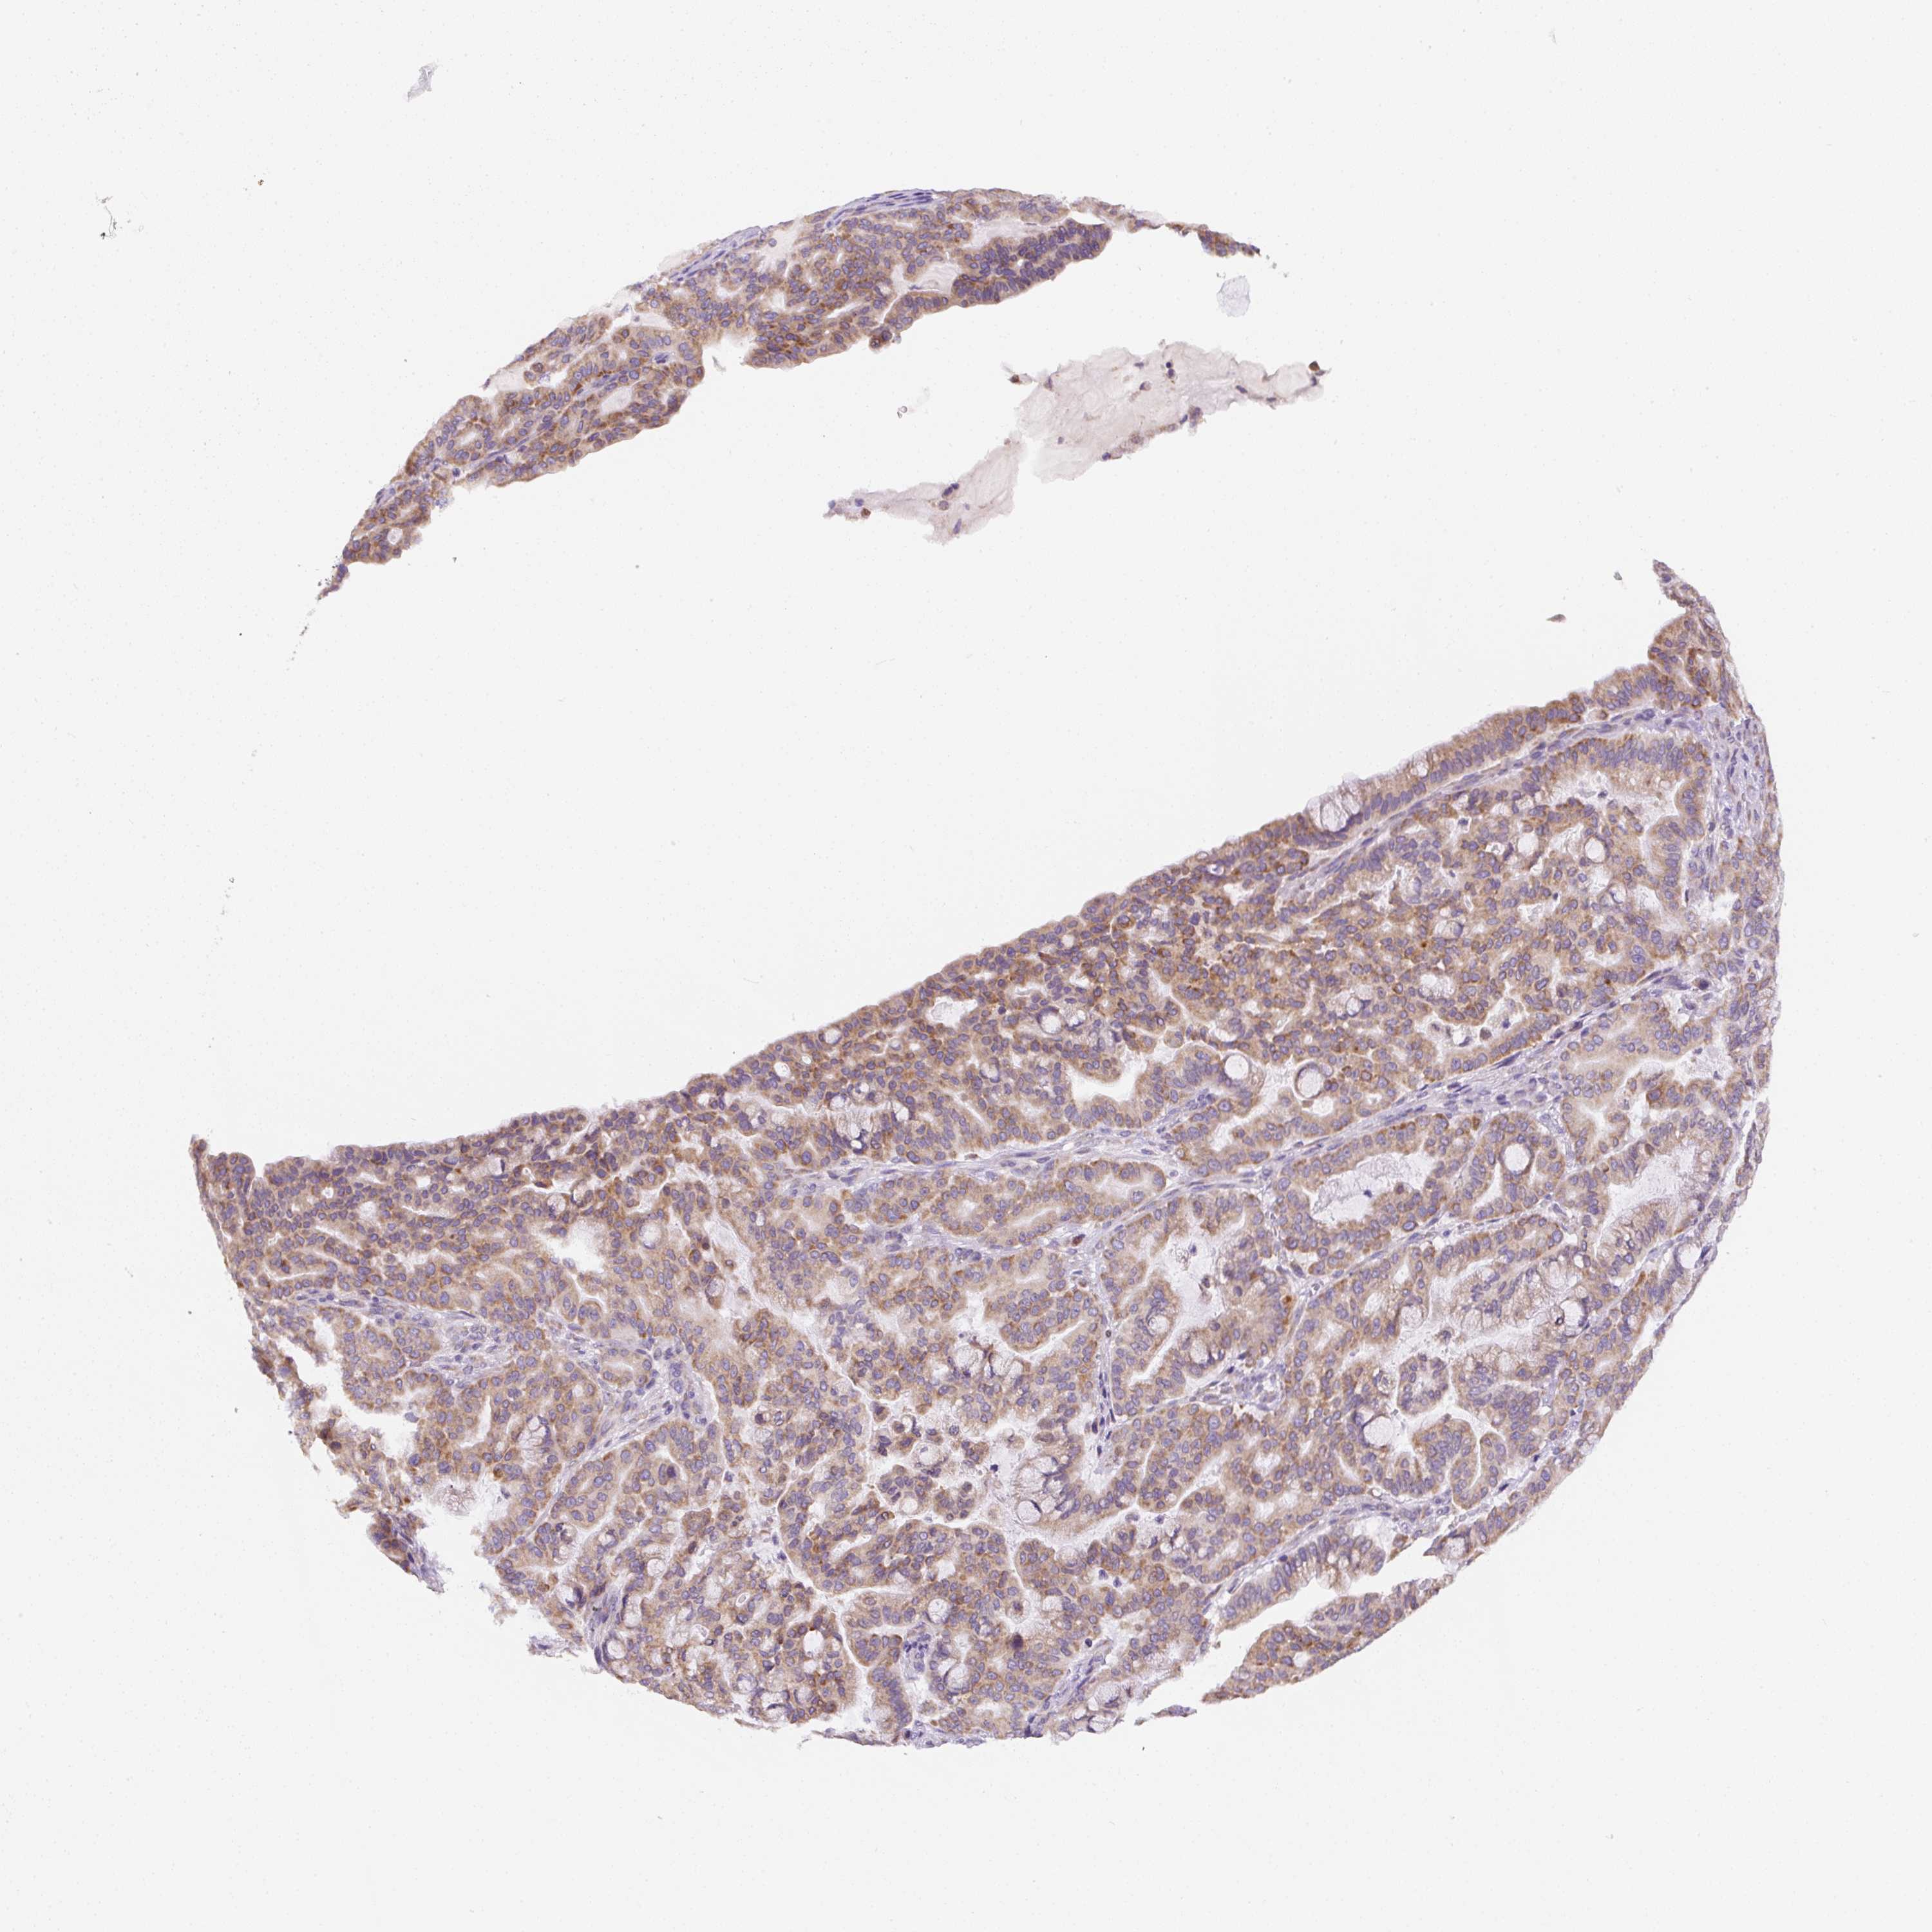

PANCREATIC CANCER - Protein expressioni

A mouse-over function shows sample information and annotation data. Click on an image to view it in a full screen mode. Samples can be filtered based on level of antibody staining by selecting one or several of the following categories: high, medium, low and not detected. The assay and annotation is described here.

Note that samples used for immunohistochemistry by the Human Protein Atlas do not correspond to samples in the TCGA dataset.

Antibody stainingi

Antibody staining in the annotated cell types in the current human tissue is reported as not detected, low, medium, or high, based on conventional immunohistochemistry profiling in selected tissues. This score is based on the combination of the staining intensity and fraction of stained cells.

Each image is clickable and will lead to virtual microscopy that enables deeper exploration of all samples and also displays staining intensity scores, fraction scores and subcellular localization as well as patient and tissue information for each sample.

Antibody HPA046841

Antibody HPA052867

Antibody CAB009746

Staining

High

Medium

Low

Not detected

Intensity

Strong

Moderate

Weak

Negative

Quantity

>75%

75%-25%

<25%

None

Location

Nuclear

Cytoplasmic/membranous

Cytoplasmic/membranous,nuclear

Adenocarcinoma, NOS

Adenocarcinoma, metastatic, NOS